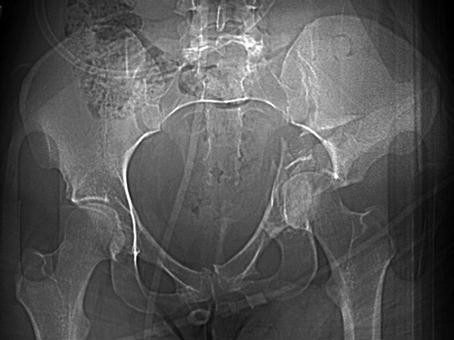

Excessive loading of the proximal femur through the femoral head causes the acetabulum to fracture. In this example, the left-sided unstable acetabular fracture fragments are displaced significantly as the proximal femur intrudes medially into the pelvis